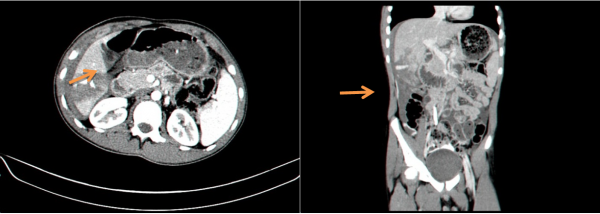

- טומוגרפיה ממוחשבת - בדיקה זו יכולה להראות את היקף הנזק ומיקומו. בדיקה זו אפשר לבצע בחולים שהם יציבים המודינמית, והיא בדיקת הבחירה (תצלום 7.10 ). ניתן להדגים גם דימום פעיל מהכבד על ידי הדגמת דליפה של חומר ניגוד באזור החבלה (תצלום 8.10).

בנוסף ב- CT אפשר לראות גם פגיעות באיברים אחרים (תצלום 9.10) כולל כלי דם (תצלום 10.10).